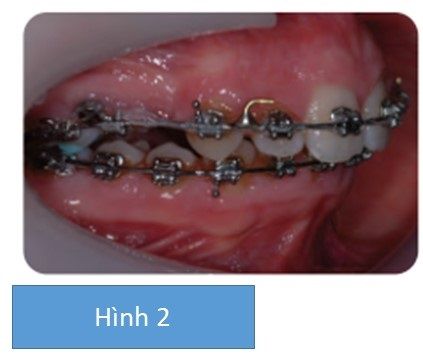

- Chỉnh nha ngụy trang với nhổ 2 răng hàm nhỏ thứ nhất hàm trên, khí cụ cố định hàm trên và hàm dưới và tăng cường neo chặn.

Vì bệnh nhân không quan tâm tới vẻ ngoài gương mặt và nét mặt nhìn nghiêng nên quyết định là ngụy trang độ cắn chìa (hình 2)